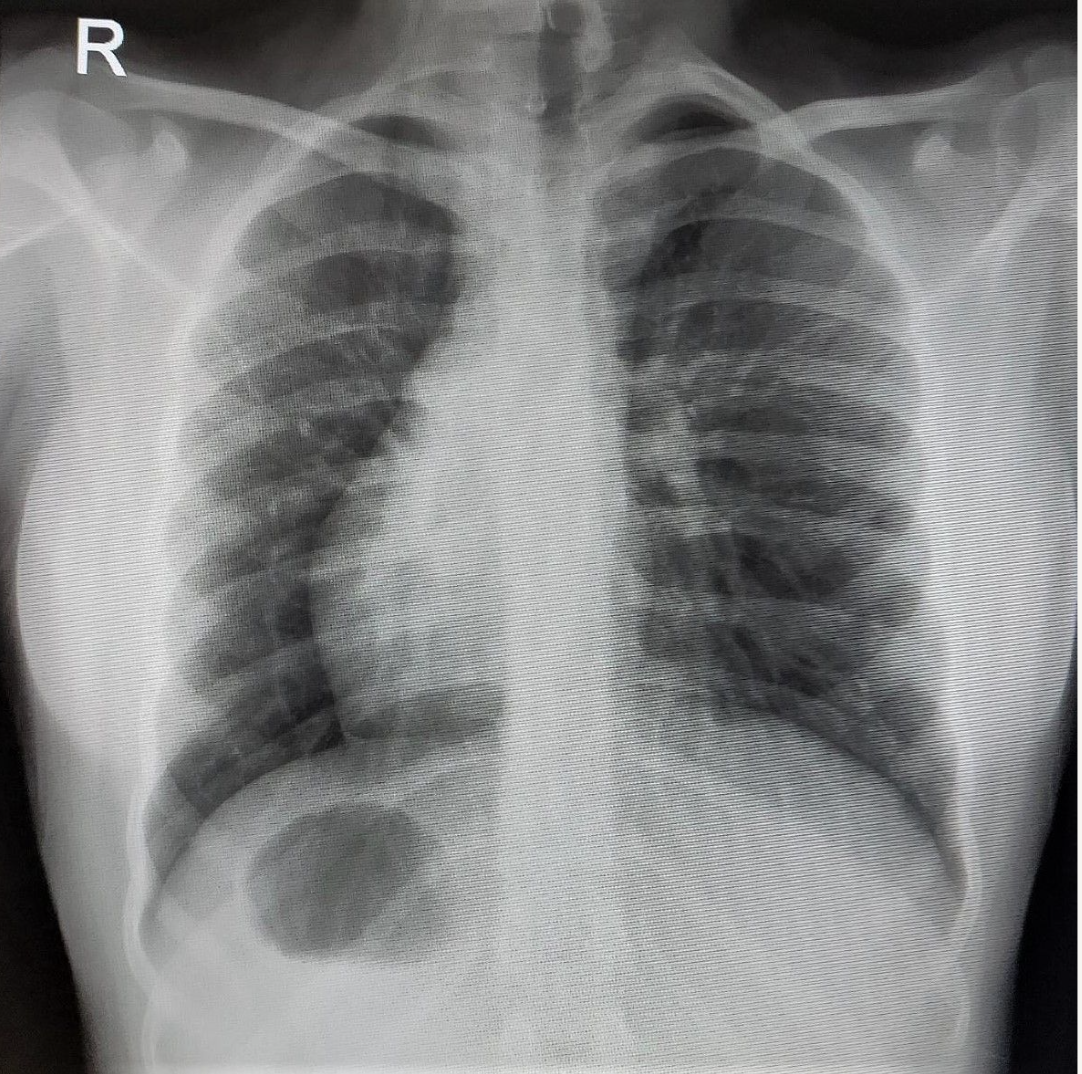

During work-up for surgery, chest radiographs revealed dextrocardia that was further confirmed on a 2D echocardiography (Figure 2). A cervical radiograph revealed the presence of hemivertebrae and butterfly vertebrae at C4 to C6 (Figure 3). Ultrasonography of the abdomen revealed situs inversus. No gastrointestinal or urogenital tract anomalies were detected. Cross-sectional imaging was not performed because the patient was asymptomatic, and echocardiography was normal. A template was constructed based on the opposite ear to guide cartilage carving intraoperatively (Figure 4).

When dextrocardia is suspected, the situs of the abdominal viscera and vessels should be determined next. Patients with situs solitus dextrocardia, as well as those with levo- or mesocardia, have a very high incidence (90%-100%) of underlying heart disorders. A systematic approach using cross-sectional imaging and echocardiography should be undertaken to look at all the different parts of the heart anatomy to identify any structural anatomic defects that may be present and affect perioperative risk. These cardiac defects commonly include the atrial septal defect, ventricular septal defect, coarctation of aorta, hypoplastic aortic arch, and patent ductus arteriosus stenosis. Patients with situs inversus dextrocardia, on the other hand, are unlikely to have intracardiac abnormalities, but they should be checked for signs of primary ciliary dyskinesia (such as Kartagener syndrome, which is seen in 25% of cases); such signs include a history of recurrent respiratory infections and evidence of poor oxygenation. Lung overinflation, bronchial wall thickening, and sinus abnormalities can all be picked up on a CT scan.6 Informed consent should be obtained from every patient with Kartagener syndrome for a possible tracheostomy before surgery to clear out residual secretions after extubation.7 Our patient had no cardiac defect nor any history of recurrent sinusitis or chest infection.